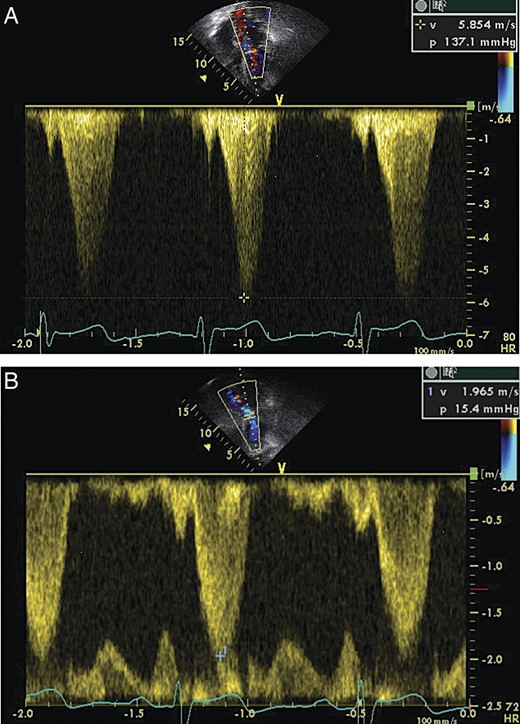

On syncope workup, Doppler assessment of the carotid artery revealed no significant obstructions, and echocardiogram demonstrated a small left ventricular cavity with hyper contractile global systolic function, mild basal septal hypertrophy and LVOT obstruction with the pressure gradient increasing from 16 mmHg at rest to 120 mmHg during Valsalva (Fig. 4).

(A) Echocardiogram demonstrating LVOT flow parameters at rest. (B) Echocardiogram demonstrating LVOT flow parameters during Valsalva maneuver, note the increase in amplitude and the ‘dagger-shaped’ flow pattern demonstrating the dynamics of LVOT obstruction.

In light of the echocardiographic findings, the patient's recurrent pre-syncope was attributed to LVOT obstruction exacerbated by Valsalva and hypovolemia (in a patient with recurrent vomiting) secondary to gastric banding. Adding to this chronic condition, acute infection and retching resulted in an acute and almost fatal exacerbation. This condition responded to esophageal decompression with resolution of the retching and relief from recurrent Valsalva. Treatment with β-blockers was initiated, diuretics were discontinued and the patient was referred to the cardiomyopathy clinic. On follow-up, several months later, the patient reported the resolution of pre-syncopal feelings though she had gained several pounds in weight.